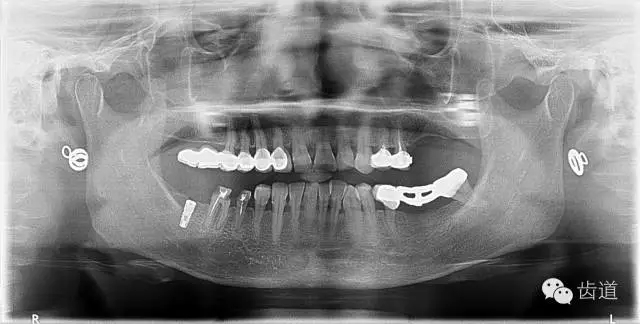

4、 全景片

2、治療后